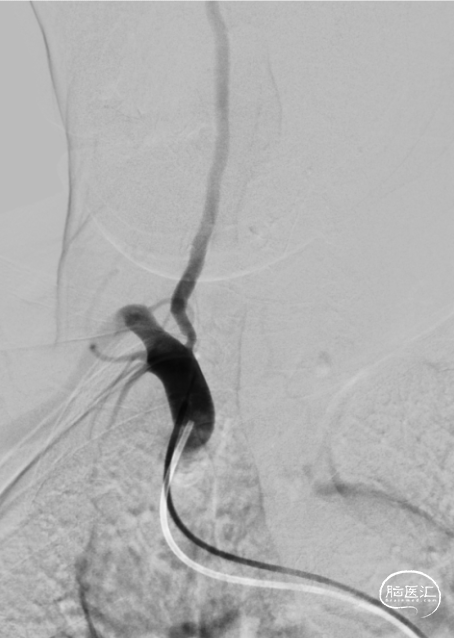

沿微导丝送入3.0mm*16mm Bridge椎动脉雷帕霉素靶向洗脱支架到达目标位置。经手推造影确认定位后,缓慢加压释放支架。

该患者双侧椎动脉起始段均狭窄,左侧更为严重,为闭塞前病变。为预防致死致残性脑卒中,行左侧椎动脉起始段支架植入术。选择Bridge椎动脉雷帕霉素靶向洗脱支架。该支架的雷帕霉素涂层可向血管内膜靶向释放药物,有效抑制支架植入术后的内膜增生,减少远期支架内再狭窄几率。同时也能有效改善后循环的血供,减少后循环脑卒中发生机会。该支架是治疗椎动脉狭窄的良好选择。